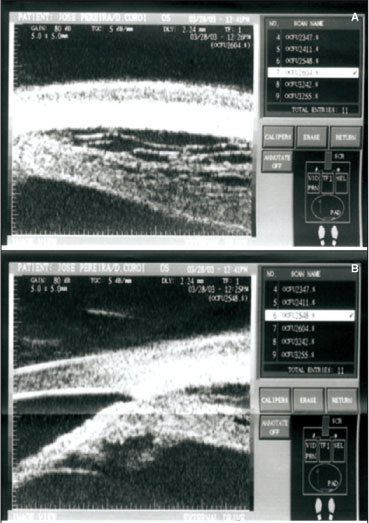

No mapeamento de retina notou-se olho esquerdo (OE) sem alterações e olho direito (OD) com descolamento de retina seroso inferior, atingindo mácula e descolamento de coróide nos 360º da periferia da retina (Figuras 1 A e B; 2 A e B).

Foi realizada angiofluoresceinografia (AGF); ultra-sonografia ocular (USG) e ultra-sonografia biomicroscópica (UBM) em ambos os olhos. À AGF notaram-se pontos de hiperfluorescência do tipo extravasamento do contraste, ao nível do EPR e no pólo posterior, que aumentaram de intensidade e tamanho com o decorrer do exame (Figuras 3 A a E). A USG ocular do olho direito denotou descolamento de vítreo parcial, espessamento de coróide e descolamento de retina na periferia (Figuras 4 A e B) e a UBM demonstrou espessamento (edema) e descolamento de corpo ciliar (Figuras 5 A a C).